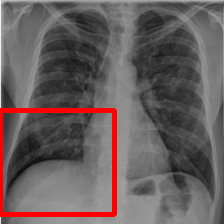

The two infected regions are symmetric.

Fig. 7: Medical image segmentation from QaTa-COV19 dataset. The text annotations are created by hand-craft.

QaTa-COV19: This dataset from Tampere University and Qatar University contains 121,378121378121,378 chest X-ray images (CXRs), including 9258 coronavirus disease 2019 (COVID-19) samples. Each image has a corresponding ground-truth mask for COVID-19 pneumonia segmentation. We choose 50 images as our training set and 10 images as our testing set. In addition, we create the text annotations for this datasets.

Fig. 7 shows the results obtained from experiments on the QaTa-COV19 datasets. Closer inspection of the figure shows that MedT has superiority in depicting long-range information. This benefits from the gated parameters. They can control the amount of information that the positional embedding supplies to key, query and value. It is noteworthy that its ability to learn the local features can still be enhanced.

GTUNet still has trouble capturing local features and depicting the exact edge shape. Inferior to GTUNet, SwinUNet can only produce rough infected regions. However, as shown in Fig. 7, it struggles to catch local details, so some incorrect areas are delineated, and the edge depiction is coarse.

UCTransNet and LViT increase their segmented accuracy. We can observe that they depict the correct infected regions of the first and second IMGs in Fig. 7. What stands out in their result pictures is that they cannot give precise edge information.

Compared with other networks, our model integrates Transformer and CNN into PPE, which ensures that it can obtain meaningful representations. After it has these powerful abilities, we combine PPE and the downstream segmentation tasks. Owing to the pretrained phase and the well-designed decoder, our model presents the most exact segmented results.

The left infected region is wider.

Fig. 11: Ablation Results of Medical image segmentation from QaTa-COV19 dataset. \daggerdenotes our model without this part.